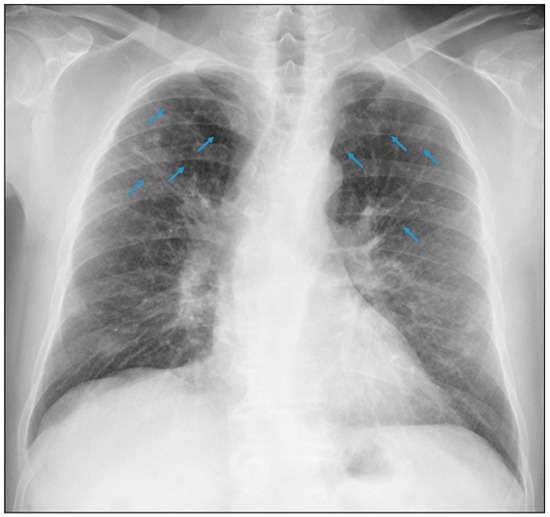

3.1.1. Case 1

3.1.2. Case 2